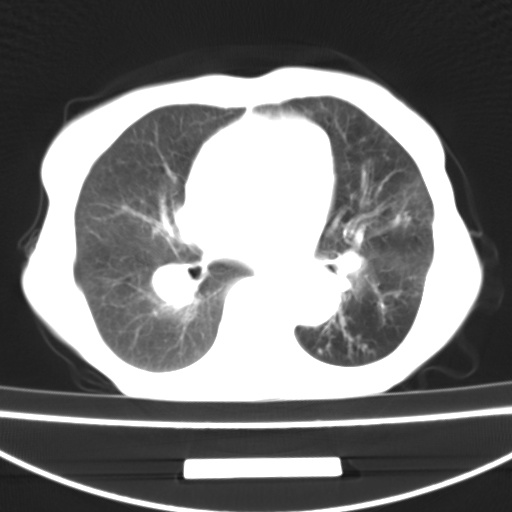

患者 女 67岁,反复咳嗽咳痰2年,加重伴喘及双下肢浮肿1月

诸大血管及f肺门血管增粗迂曲.左下肺多发薄壁空腔影.部分非也透亮度增高.薄曾扫描可区分肺气肿类型.考虑1.慢性支气管炎 2.左下肺支气管扩张 3.肺气肿 4 肺动脉高压5.是否有先心病病史

考虑1.慢性支气管炎 2.左下肺支气管扩张 3.肺气肿 4 肺动脉高压

慢支炎、肺气肿、双肺感染、左下囊状支扩。

慢支、肺气肿、肺动脉高压;左下肺囊状支扩并粘液栓形成。